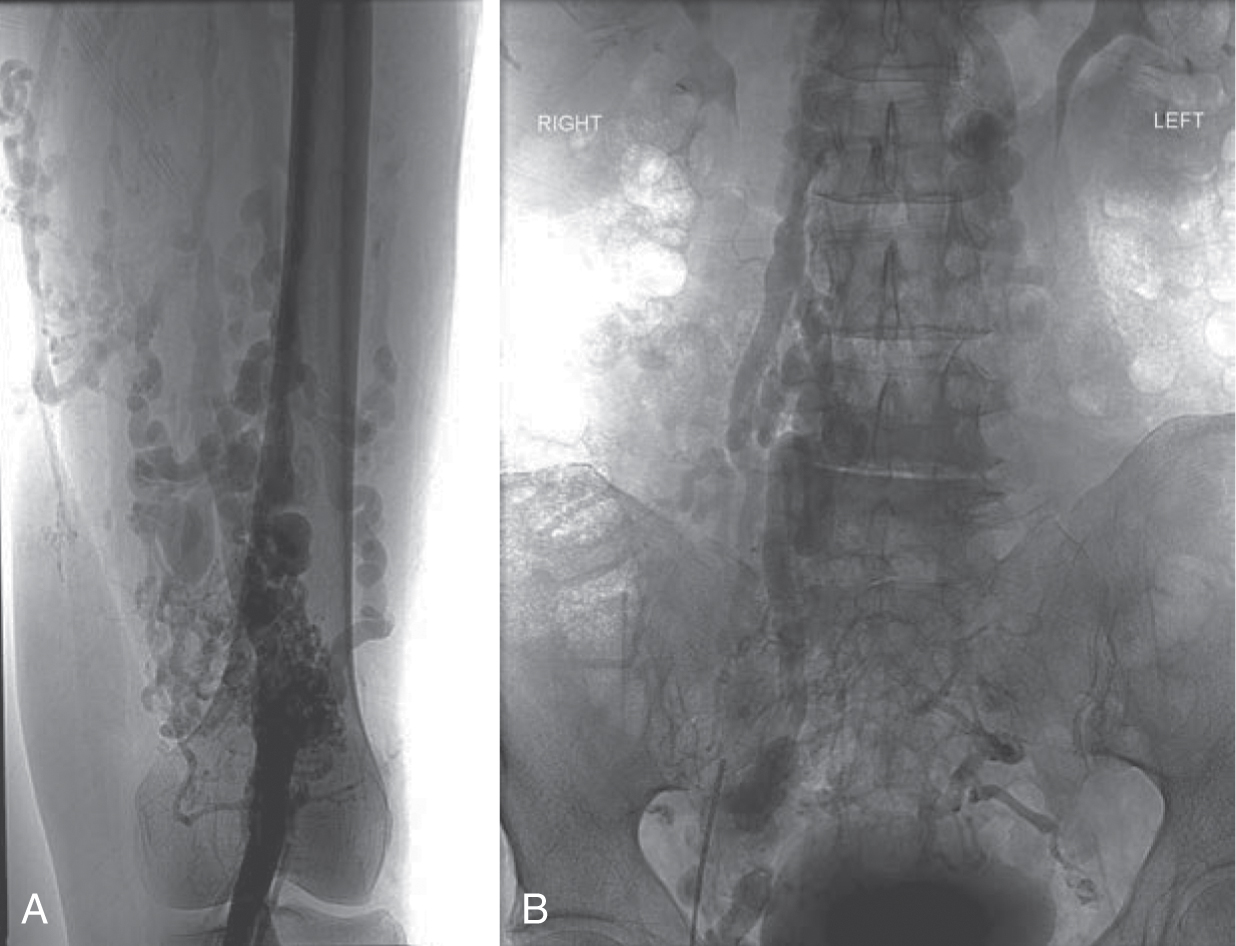

Bệnh động mạch ngoại biên (PAD) là một bệnh của quá trình lão hóa với tỷ lệ hiện mắc là 10% ở người trên 65 tuổi và 30% ở người ở độ tuổi 80, biểu hiện bằng chứng đau cách hồi hoặc các triệu chứng thiếu máu chi nguy kịch. Các triệu chứng thường xuất hiện ở phần xa so với mức độ hẹp. Nếu bệnh nhân hoạt động, đau cách hồi là triệu chứng điển hình; nếu bệnh nhân không hoạt động, PAD có thể biểu hiện bằng đau khi nghỉ, loét, đỏ da khi hạ thấp chi, hoặc hoại tử (Hình 25.1). Khi chứng đau cách hồi tăng đột ngột, phải xem xét đến huyết khối tại chỗ hoặc một biến cố thuyên tắc. Biểu hiện lâm sàng của xơ vữa động mạch tắc nghẽn (tắc động mạch cấp tính) được mô tả bằng sáu chữ P: pain (đau), pallor (xanh xao), paresthesia (dị cảm), paralysis (liệt), pulselessness (mất mạch), và polar (cảm giác lạnh). Chi có nguy cơ bị cắt cụt nếu lưu lượng máu không được phục hồi kịp thời (Hộp 25.2).